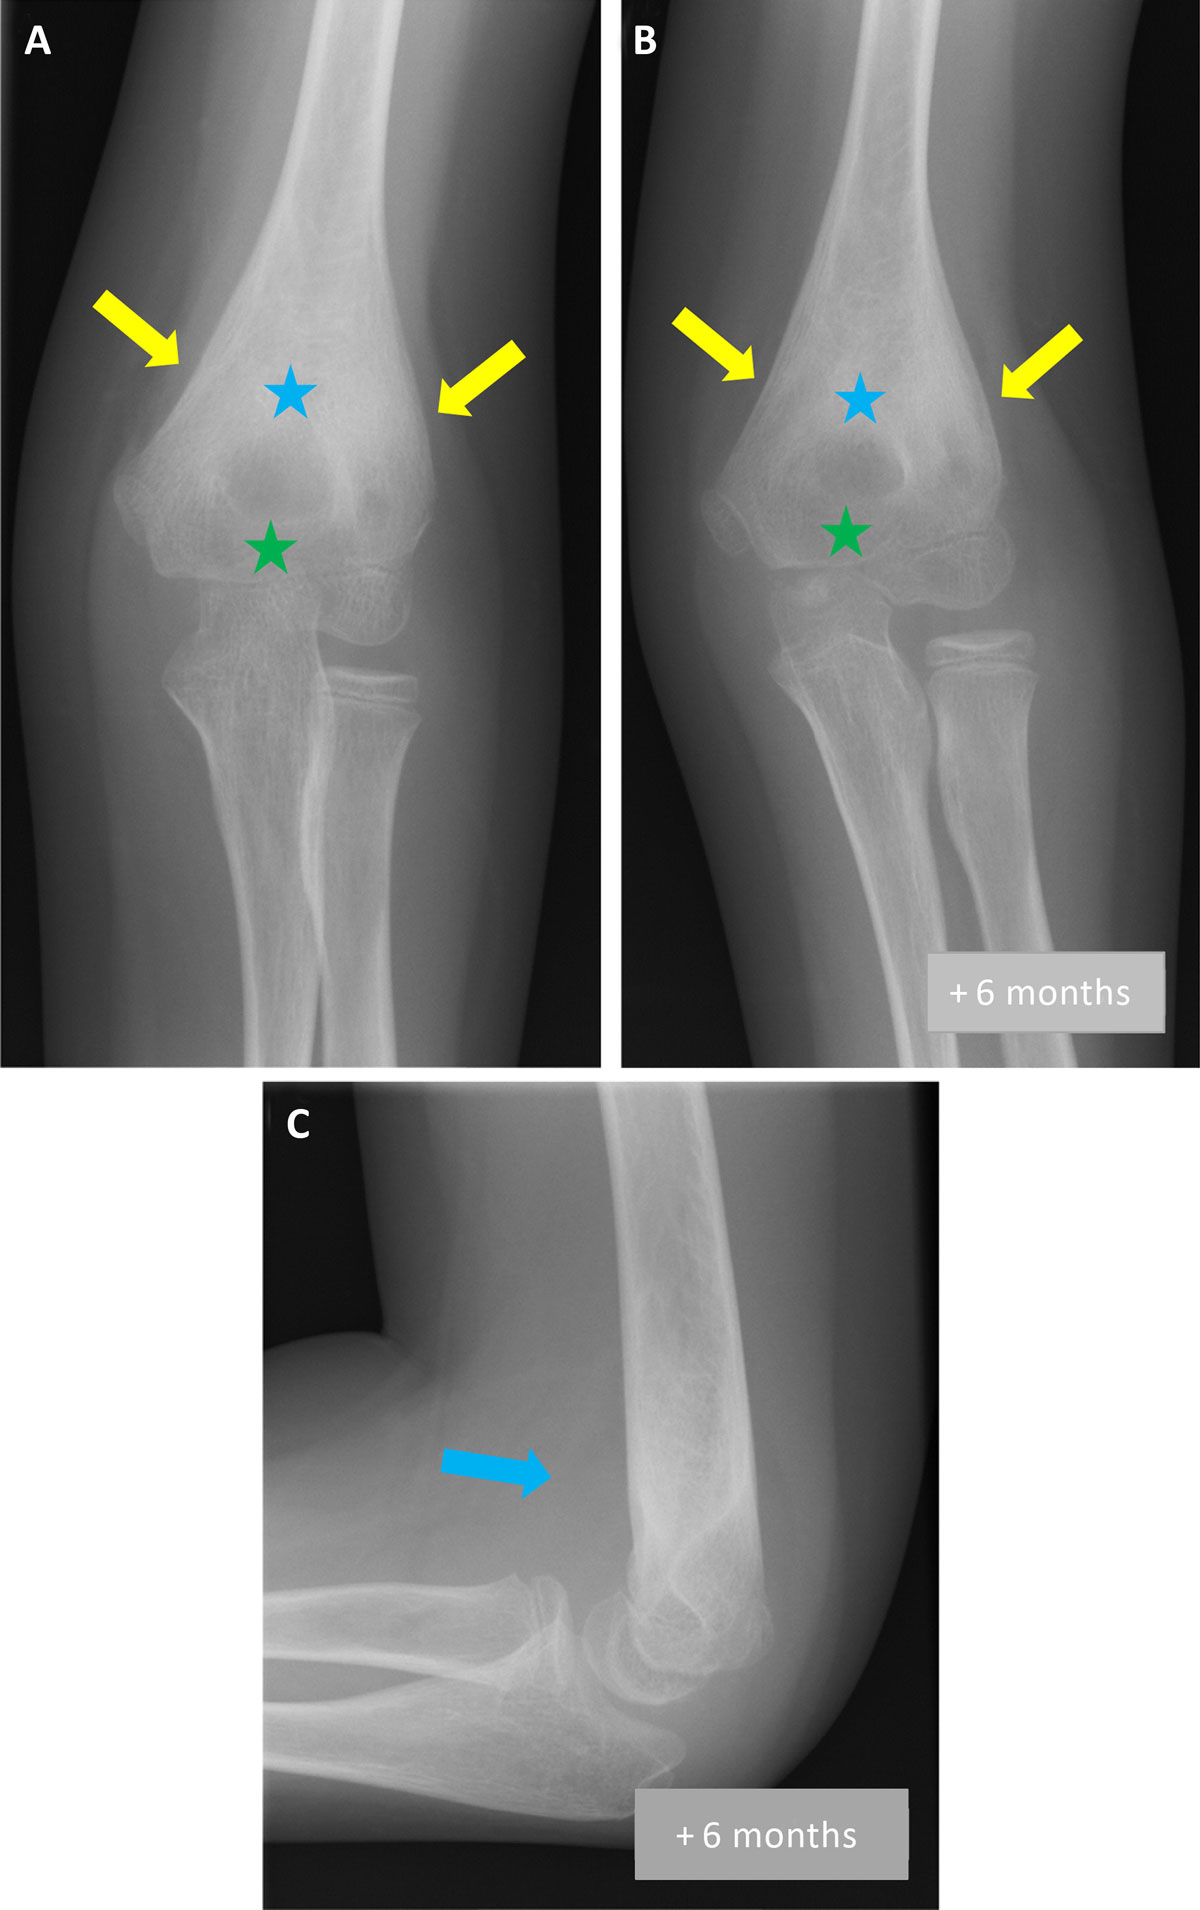

Three months later, as the symptoms persisted, a new ultrasound of the elbow was performed, demonstrating joint effusion (asterisk on Figure 1B); elbow radiograph on the same day showed metaphyseal sclerosis (blue asterisk on Figure 2A), peri-articular osteopenia (green asterisk on Figure 2A) and periosteal apposition (arrows on Figure 2A). Septic arthritis was suspected and a joint lavage was performed; bacteriological samples were negative. Treatment with ledertrexate for chronic synovitis was started.

Figure 2

Six months later, the swelling and the limitation of movement persisted. X-ray showed an increase in metaphyseal sclerosis (blue asterisk on Figure 2B) and peri-articular osteopenia (green asterisk on Figure 2B), incorporation of periosteal apposition (arrows on Figure 2B) and intra-articular fluid (arrow on Figure 2C). Given these findings, the diagnosis of JIA was reconsidered. Repeat blood tests revealed an inflammation with slightly increased C-reactive protein (CRP) and leukocytosis. These results, in correlation to the X-ray, raised the suspicion of chronic osteomyelitis and magnetic resonance imaging (MRI) of the elbow was performed.